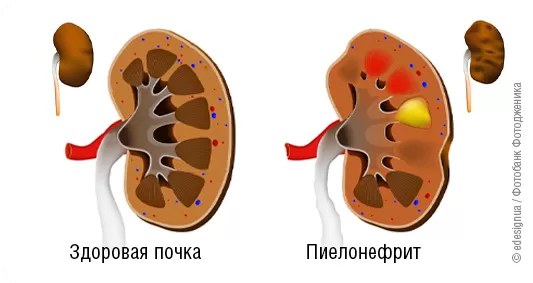

Интраренальная лоханка: рентгеновские снимки и примеры